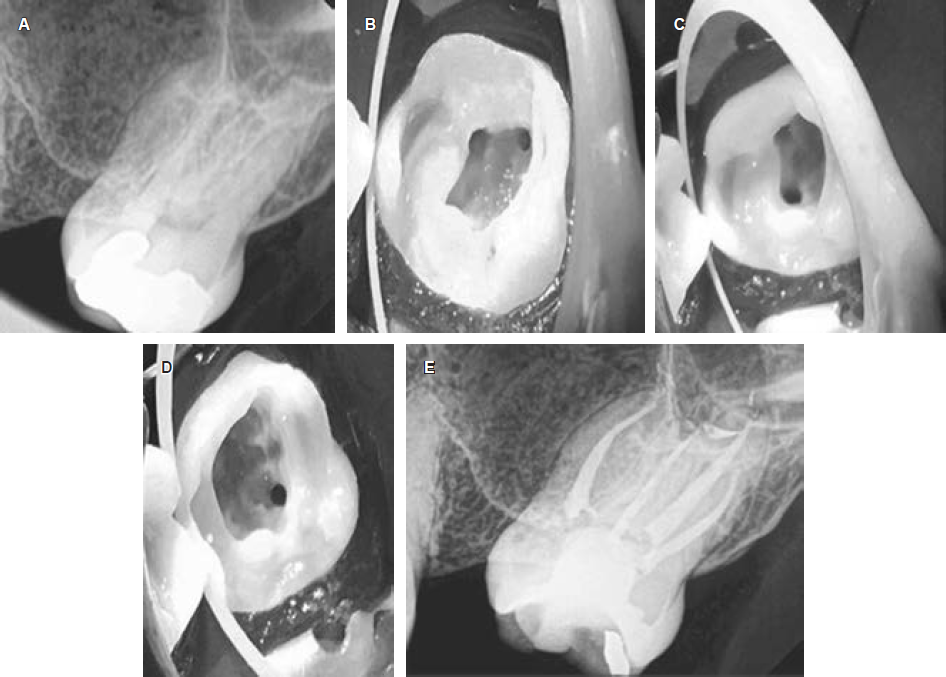

Después de la técnica de anestesia local con lidocaína con epinefrina al 1:80,000, el tratamiento de conductos se realizó con aislamiento absoluto con dique de hule y aumento a través de lupas (3.5x). La cavidad de acceso se efectuó con fresas de carburo y fresas Endo-Z (Dentsply Maillefer, Ballaigues, Suiza). No se observó presencia de grietas o líneas de fractura. Al principio se ubicaron tres conductos radiculares utilizando un explorador DG16 (Hu-Friedy, Chicago, IL, USA), pero el conducto palatino se localizó más distalmente de lo normal, y eso hizo sospechar al operador de la presencia de un conducto radicular adicional. Por lo tanto, se realizó una inspección cuidadosa del piso de la cámara pulpar y se amplió ligeramente la cavidad de acceso en sentido mesiopalatino. Una vez localizados los cuatro conductos radiculares, se negoció cada uno con una lima 10/02 (Dentsply Maillefer, Ballaigues, Suiza). Se tomó la longitud de trabajo con un localizador de ápices (Root ZX, J. Morita, Tokio, Japón) y se confirmó con una radiografía dentoalveolar digital. La instrumentación se realizó con el sistema Reciproc® (VDW, Alemania) con la técnica sugerida por el fabricante y se complementó con el sistema Mtwo® (35/05) (VDW, Alemania). Se utilizó el mismo protocolo de instrumentación para los cuatro conductos radiculares. La desinfección se realizó con NaO-Cl a 5,25% activado por ultrasonido (tres ciclos de 20 segundos) y EDTA a 17% (Asia Chimi Teb, Teherán, Irán). Después de la irrigación con EDTA se irrigó con solución salina al 0.9% para desactivar al EDTA. Por último, se usaron 20 mL de NaOCl al 5.25% para irrigar cada conducto radicular utilizando un sistema de presión negativa apical como el Endovac® (SybronEndo), esto como protocolo de irrigación final. La técnica de obturación se realizó mediante la compactación de onda continua y sellador AH + (Dentsply Maillefer, Ballaigues, Suiza) (Figura 1A-C).

La identificación radiográfica preoperatoria de una raíz adicional tiene algunas dificultades. Estas dificultades pueden incluir la superposición de estructuras anatómicas como se observa en las radiografías preoperatorias de los dos casos presentados.13 Si el contorno de las raíces no se observa claramente en una radiografía, se deben tomar más radiografías con diferentes angulaciones para identificar o descartar la presencia de variaciones anatómicas (Figuras 1A y 2B). Algunas de las técnicas de angulación para tomar radiografías han sido revisadas previamente por Fava y colaboradores.13 Las radiografías siempre tendrán ciertas limitaciones, independientemente de las técnicas de angulación utilizadas, la imagen radiográfica es una sombra y es una representación bidimensional de un objeto tridimensional.14 A pesar de estos desafíos, las radiografías dentoalveolares preoperatorias de buena calidad podrían ser muy útiles en la identificación de características radiográficas (como la lámina dura y el ligamento periodontal) que pueden interpretarse de manera más consistente que otras15 y que nos puede proporcionar información para una mejor determinación del número y la forma de las raíces en los molares superiores.16 Cuando las raíces de los dientes parecen ser más largas que la longitud promedio (20 mm) o la longitud máxima (24 mm), esto puede ser una indicación de una raíz adicional (Figura 1A-C ). Por ejemplo, algunos casos reportan segundos molares maxilares con dos raíces palatinas con una longitud de la raíz palatina igual o superior a 26 mm.17 Por lo general, utilizando la técnica de ángulo de bisección estándar, la raíz palatina se puede ver detrás y en el medio de la raíz distobucal y mesiobucal en una radiografía. Si la raíz palatina no se pudiera identificar en la posición mencionada anteriormente (Figuras 1A y 2A), esto sería una indicación de una variación anatómica como la presencia de una raíz palatina adicional. Para una correcta identificación de la raíz palatina en esta situación es aconsejable tomar más radiografías que modifiquen la angulación vertical u horizontal para obtener una imagen no superpuesta de las estructuras de interés (Figuras 1C y 2C). La radiografía de la longitud de trabajo también puede confirmar la presencia de dos raíces palatinas si el instrumento parece estar alejado del centro de la raíz.18,19